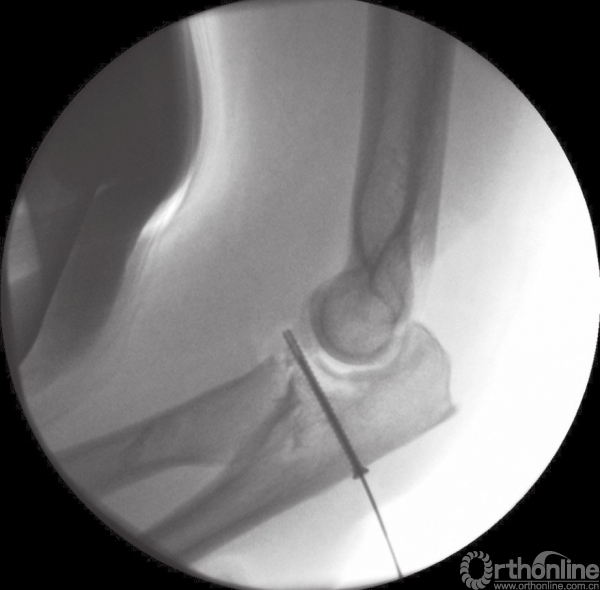

如果冠状突骨折块足够大,从外侧入路可以直接观察到,尤其是通过桡骨头的缺损处或者在桡骨头切除后。因此,在复位桡骨头之前先处理冠状突骨折,冠状突骨折块可以通过牙科刮匙进行复位和维持,然后经皮从尺骨背侧面置入空心螺钉进行固定。如果外侧入路进行固定存在困难,可以考虑直接由内侧入路进行暴露。小的游离骨折块可以去除(图4),套锁缝合前关节囊至尺骨可以加大稳定性(图5)。

图6 间接复位冠状突骨折块